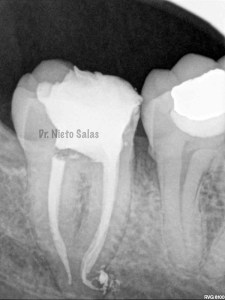

La otra pieza, el 3.7, se instrumentó con sistema Protaper y obturación con Ola continua de Calor y un back-filling con la pistola Obtura II.

Y una en las demás proyecciones MESIO Y DISTO:

2. disculpe, en las imagenes de la entrada de los conductos, era dos conductos distales o era solo uno ?? muchas gracias y enhorabuena por el casa, es perfecto !!

3. Dr Nieto Salas, en la imagen en que se ven la camara con la entrada de los conductos y la gutapercha, el orificio de entrada en distal era muy ancho, a parte de conductos laterales, localizo un conducto o dos conductos ?? ( la duda es por lo ancho de la entrada). El caso es maravilloso. Le doy mi enhorabuena.

4. Hola Juan,

en ese caso en particular, el número de conductos era solamente uno, ya sabes que los conducto distales en muchas ocasiones tienen forma ovalada, con lo que la entrada puede corresponder con las imágenes.